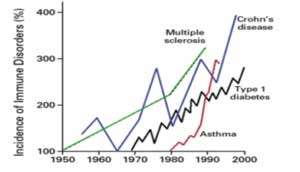

One out of two Americans suffer from immune disorders. If we look attentively at the changes occurring in our environment, we will notice some trends running in parallel: an exponential increase in chronic diseases, a similarly exponential trend of increasing strain on our immune system, but also an exponential increase in organic nutritional and behavioral concepts (Figure 1 and Figure 2).

Chronic diseases, such as cancer, ALS, Alzheimer’s disease, Parkinson’s disease, MS, Crohn’s disease and chronic fatigue syndrome, Breast Cancer are increasing at an explosive rate, and extrapolation of the curves shows that within a few years, everyone living in the Western world will be affected by at least one of these diseases.